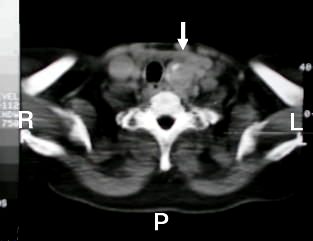

Tomografia del Cuello y del Tórax

tomografia cervical bocio intratoracico

Corte Tomográfico "A"

Corte torácico alto: Se aprecia el aspecto sólido de la lesión con áreas heterogéneas mas claras, con calcificaciones que recuerda las características tomográficas del bocio multi-nodular difuso. de 6 cm longitudinal x 5 cm AP. x 4 cm transversal.

Corte Tomográfico "B"

Corte 2 cm mas bajo: La lesión redondeada, capsulada, de 4 x 5 cm de diámetro, que se proyecta en el tórax, para-traqueal izquierda con dezplazamiento lateral derecho de la traquea.